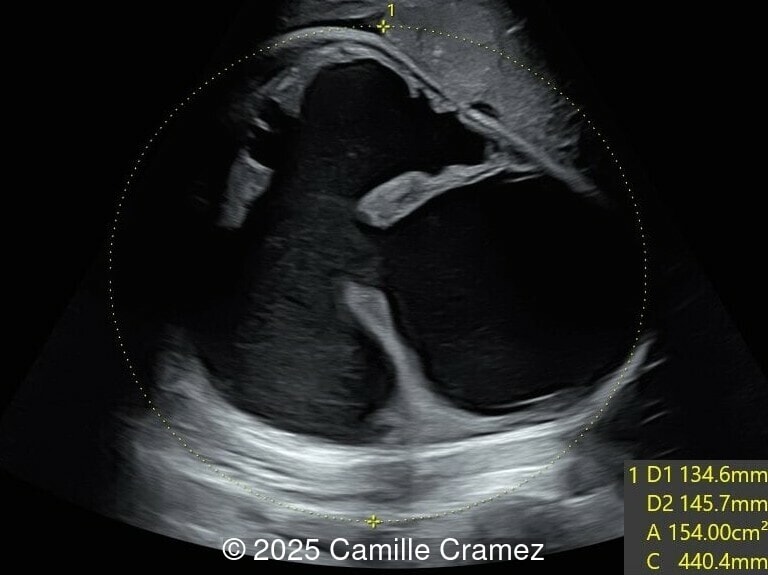

At 36 weeks gestation, the abdominal findings were unchanged however, the bones appeared short (<1st percentile) and the spine had an unusual appearance, therefore a computed tomography was performed at 37 weeks gestation.

Our prenatal ultrasound revealed a male fetus with megabladder, dilation of both ureter and kidneys, and thinned kidney parenchyma consistent with Lower Urinary Tract Obstruction (LUTO). Additional findings suspected on ultrasound and confirmed on computed tomography included:

- Suspicion of dilated bowel in the left flank, in addition to dilated urinary tract

The diagnosis of PBS is often made in the second trimester of pregnancy, although it has been described as early as 11 weeks of gestation [20]. The most frequent ultrasound findings are a large, thin-walled bladder accompanied by bilateral hydroureter/hydronephrosis, dysplastic kidneys with echogenic renal parenchyma and renal cortical cysts, and abdominal wall laxity which is better viewed after bladder decompression [21]. Cryptorchidism can be detected prenatally by 28 to 30 weeks gestation when the testes descend into scrotum. There may be a patent urachus, visible as a cystic connection between bladder and umbilicus. Oligohydramnios is a frequent finding, which makes it difficult to visualize the associated anomalies.